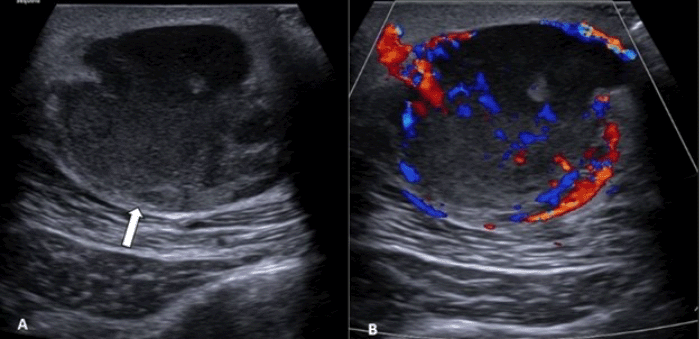

Figure 3. Ultrasound Imaging of the Dorsal Mass. Published with Permission

(A) Grayscale ultrasound image demonstrates a round, heterogeneous, echogenic mass located within the subcutaneous fat, exerting mass effect on the underlying latissimus dorsi muscle (arrow). (B) Color Doppler imaging of the mass shows evidence of both peripheral and internal arterial and venous flow, indicative of significant vascularity and making a simple abscess or hematoma unlikely

Intraoperatively, the cavity was found to contain a gelatinous white fluid, without evidence of frank pus or foul odor, prompting a biopsy for pathological assessment. Histopathology revealed a pleomorphic spindle cell neoplasm with significant mitotic activity (15 mitoses/10 high-power fields) and scattered areas of necrosis estimated at 10-20% of the tumor volume. Immunohistochemical (IHC) staining was positive for CD163 and CD68, with focal positivity for smooth muscle actin (SMA). Stains for desmin, pan-keratin (AE1/AE3), CD34, and myogenin were all negative (Figure 2). These findings narrowed the histological differential diagnosis to atypical fibroxanthoma (AFX) and pleomorphic dermal sarcoma (PDS). Upon retrospective review, the initial ultrasound was likely misinterpreted, as evidence of both peripheral and internal flow was indicative of a vascularized mass, making a simple hematoma or abscess less likely (Figure 3).